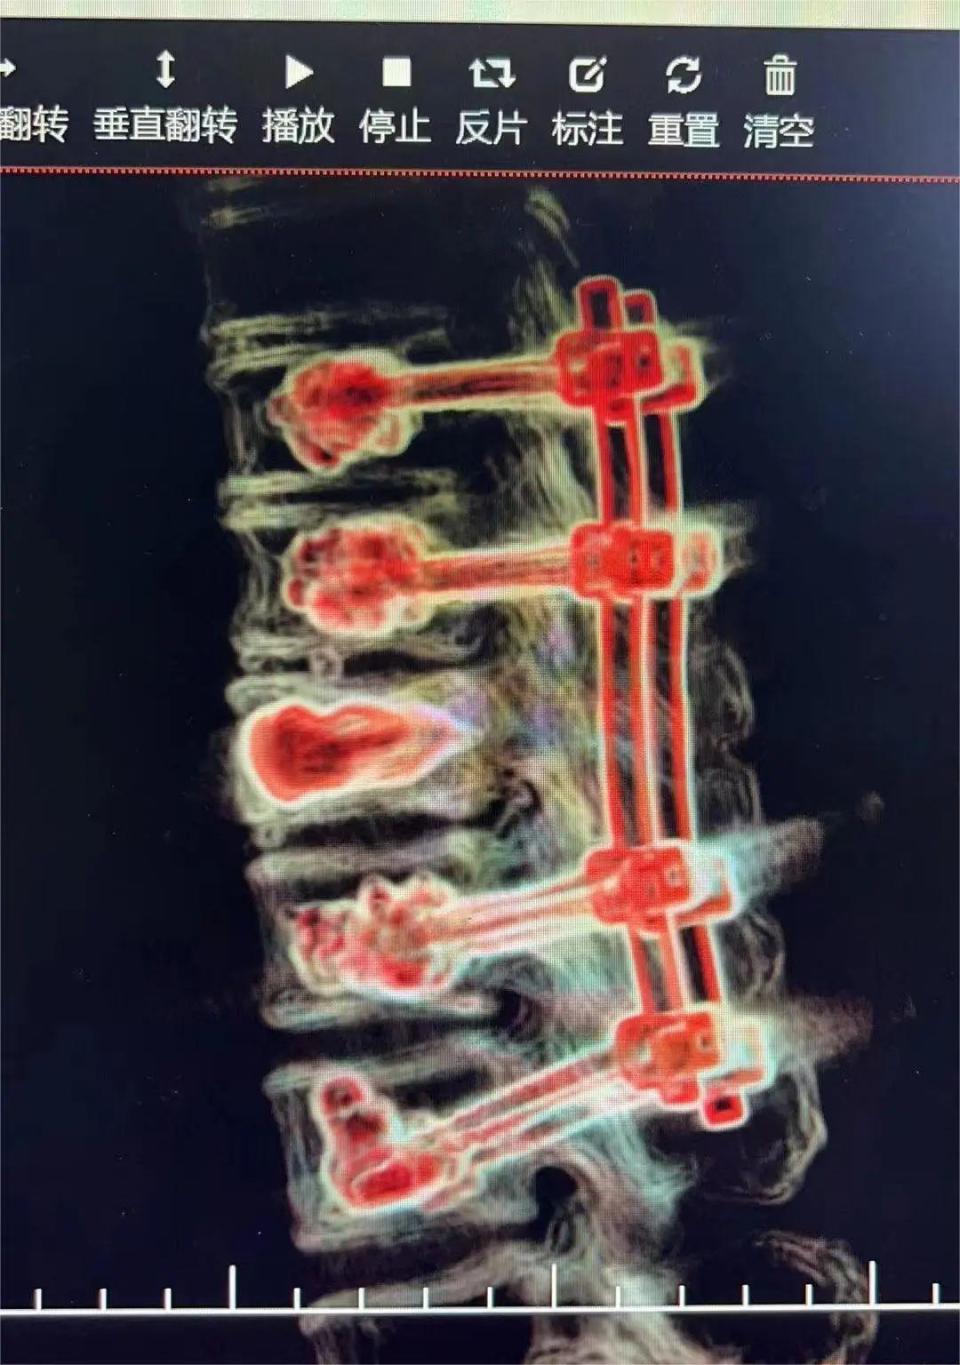

经神经脊柱外科多次术前讨论,在岳阳市人民医院钟炯彪主任医师指导下,决定为患者实施经皮骨水泥螺钉+伤椎椎体成形术。

术中、术后影像(8钉2棒)